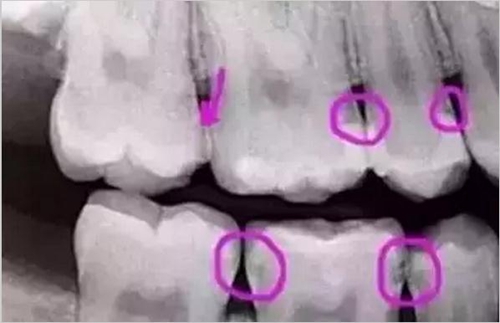

圈出來的地方或多或少都有點(diǎn)齲齒,但是有些你并不能看見。這些齲齒還淺不會(huì)讓你有什么感覺,頂多吃東西塞牙,和冷水敏感而已。